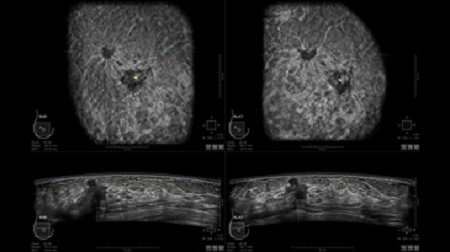

GE INVENIA ABUS – это современный УЗИ аппарат, который создан для точной и эффективной диагностики сканирования с высокой плотностью молочных желез. Выявляемость патологий раковых и предраковых стадий заболевания составляет 55%, что в конечном счете позволяет ставить врачу точные и своевременные диагнозы. Традиционные методы использования маммографии не показывают такой выявляемости, ограничиваясь лишь 3-38%.

УЗИ-аппарат GE INVENIA ABUS позволяет проводить максимально операторонезависимые процедуры, что значительно снижает риск неправильной постановки диагноза и сопутствующие издержки на обработку информации. Система готовит отчет в течение 3-х минут после сканирования, это безусловное преимущество по сравнению с обычным УЗИ сканером.

• датчик с изогнутой апертурой для качественного исследования

• сканирование одной грудной железы в трех проекциях не более 60 сек.;

• обработка результатов за три минуты.

Возможности встроенной УЗ-системы:

• Увеличение или уменьшение степени сжатия грудной железы;

• Функция автоматического сканирования активируется одним нажатием;

• Возможность отмены сканирования;

• Глубина проникновения УЗ-лучей – до 50 мм;

• Одно детализированное изображение можно получить менее чем за 1 минуту

• Многорядная светодиодная подсветка;

• Встроенный сверхширокий вогнутый датчик С15-6ХW.